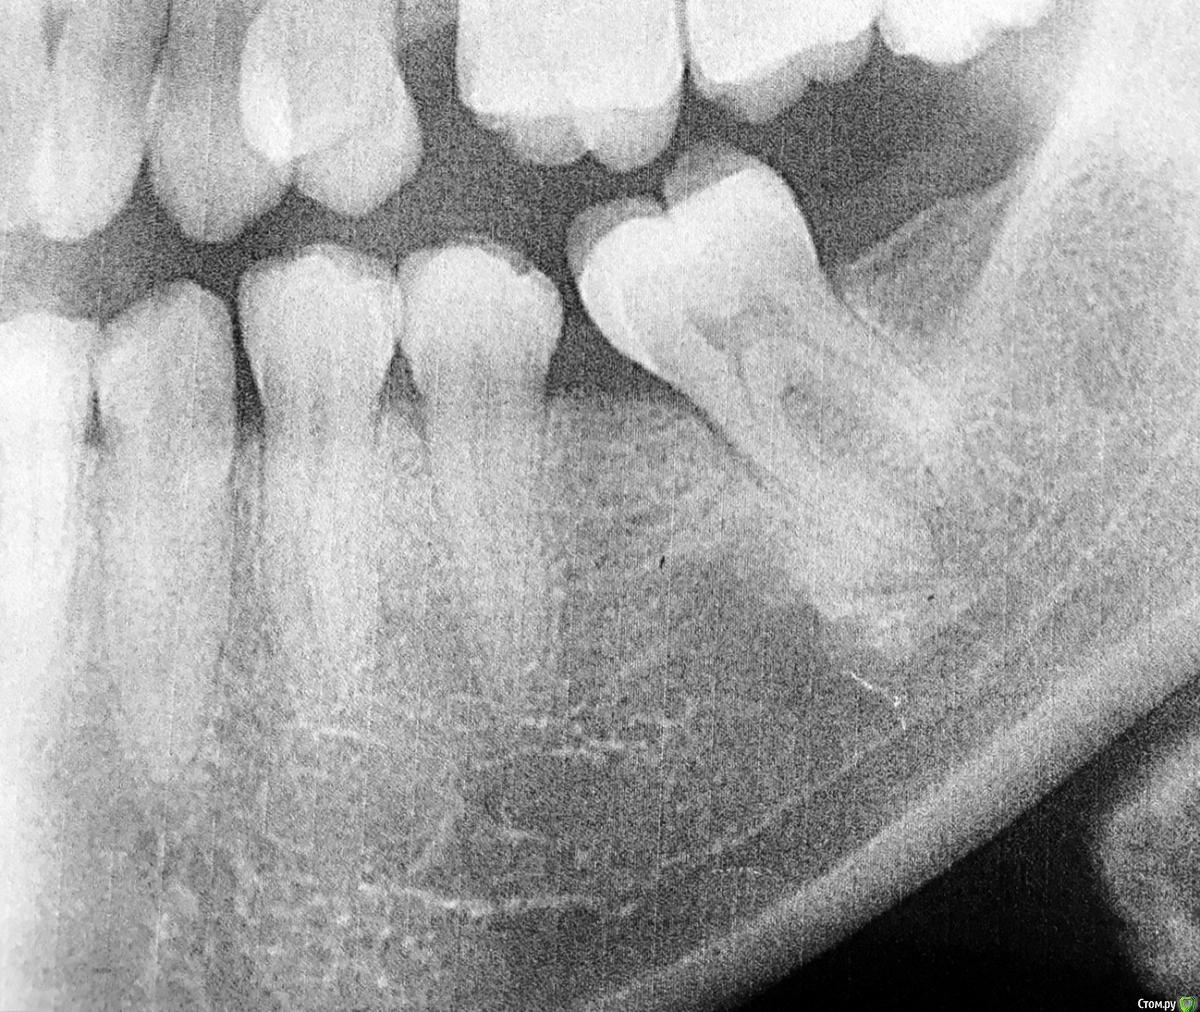

alenakot Опубликовано 13 октября, 2015 Автор Поделиться Опубликовано 13 октября, 2015 (изменено) снимок кисты..2 раза направляли удалять.. но я как то мимо ушей, ребенок маленький времени нет, ортопонограма доктор сказал плохо сделали, типа кму не видно. еще кстате зуб болит этот периодически то болит то не болит. десна припухает на утро спадает... жевать на нем могу, но когда болит то жевать больно..] Изменено 13 октября, 2015 пользователем alenakot Ссылка на комментарий

red_butler Опубликовано 13 октября, 2015 Поделиться Опубликовано 13 октября, 2015 Кисту не вижу, нужно искать другую причину лимфаденопатии и исключить дисфункцию сустава. Ссылка на комментарий

red_butler Опубликовано 13 октября, 2015 Поделиться Опубликовано 13 октября, 2015 http://s003.radikal.ru/i202/1510/e9/d751e19cb8e7.jpg вот чотко сняла)Маникюр хороший, а снимок нет. Зуб вроде интактный, но есть пародонтальный карман связанный с наклоном зуба. Ссылка на комментарий

St. Опубликовано 13 октября, 2015 Поделиться Опубликовано 13 октября, 2015 Подозреваю, что врачей беспокоит это образование. Но по такому снимку сказать что-то конкретное нельзя. Переделайте снимок, а лучше сделайте КТ. Ссылка на комментарий